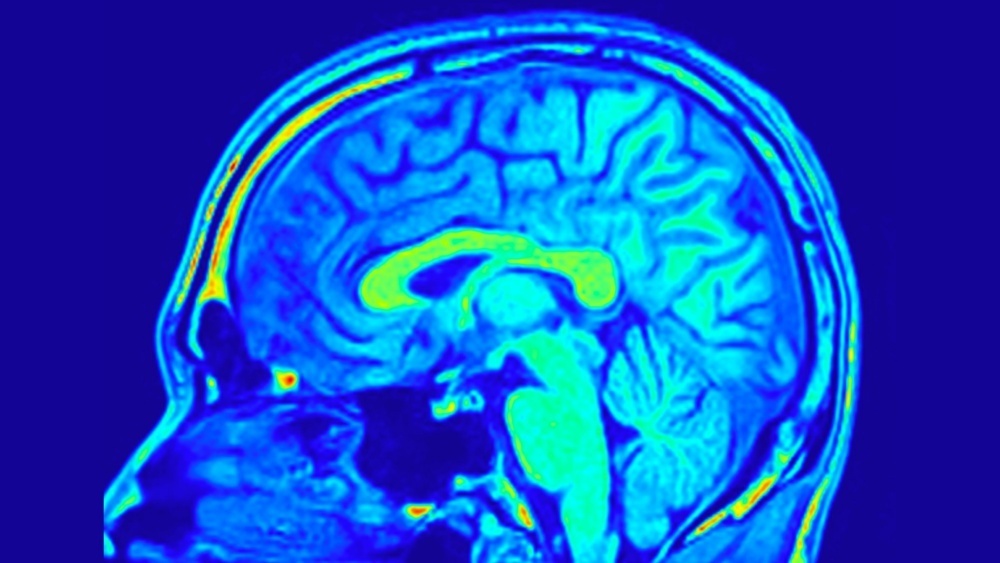

Белое вещество мозга — это сеть коммуникационных путей, по которым нервные сигналы передаются между его областями. Именно от эффективности этих связей зависит, насколько быстро человек думает и как хорошо справляется с задачами.

Новое исследование пошло глубже. Ученые использовали современные методы нейровизуализации — NODDI (оценка плотности и ориентации нейритов) и карту миелиновой воды. Это позволило рассмотреть структуру мозга с беспрецедентной точностью.

Результаты оказались любопытными. Люди с более высокими генетическими показателями интеллекта имели большую плотность нейронных отростков в ряде зон белого вещества. При этом именно эта особенность — а не степень миелинизации или ориентация волокон — объясняла разницу в умственных способностях.

Наиболее важными оказались связи между областями, отвечающими за язык, память и когнитивный контроль — в частности, верхний продольный и крючковидный пучки, а также поясная извилина.